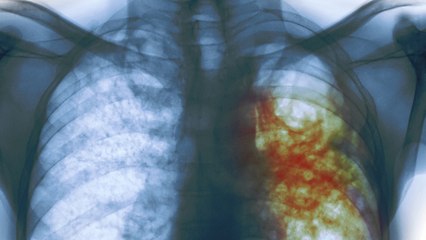

Toxoplasmosis is an infection caused by a parasite. This parasite is called Toxoplasma gondii. It can be found in cat feces and undercooked meat, especially venison, lamb, and pork. It can also be transmitted through contaminated water.